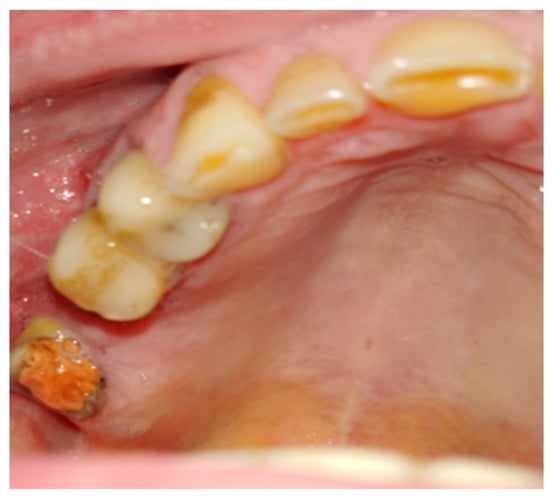

Figure 1. A case after the removal of the first upper right molar and curettage of some periapical inflamed tissue resulting in the loss of buccal cortical plate and opening of a huge oro-antral communication (CBCT scans in sagittal view).

Figure 2. The bone defect with visible buccal cortical bone loss. In this case, when the patient is not willing to undergo any dental implant rehabilitation, it is possible to suture the BFP in a double-layer technique to fully close the bone deficiency and cover it with a sliding muco-periostal flap.